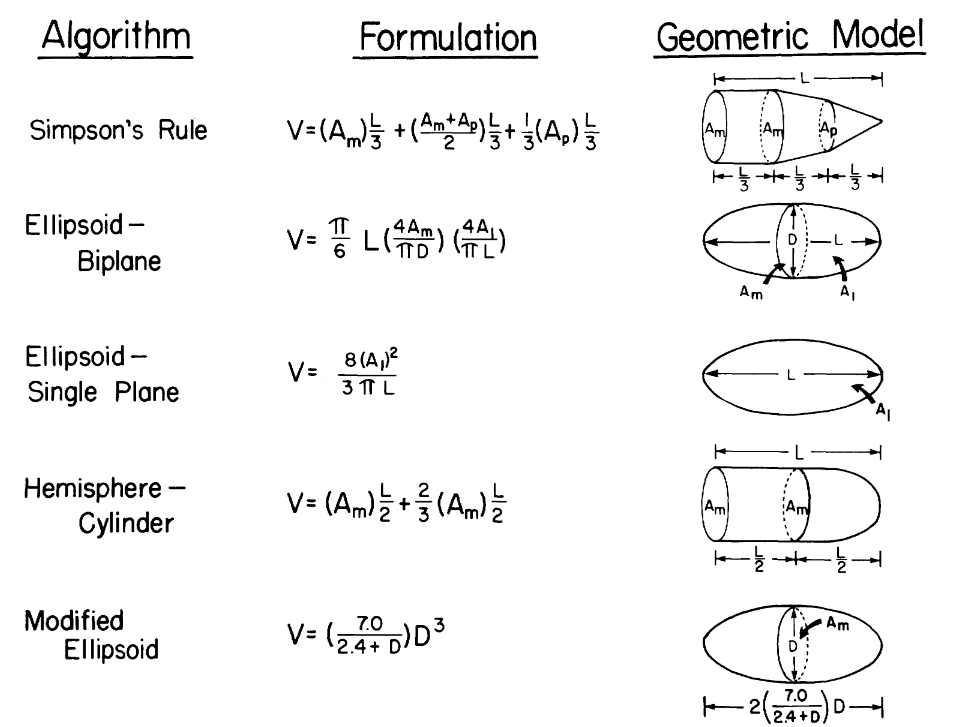

Meanwhile, there are alternative algorithms to calculate the volume that require fewer slices to be obtained, each assuming different geometric model for the ventricle. For instance, the modified Simpson's rule, which consider the ventricle as the sum of a cylinder (from the base to the mitral valve), a truncated cone and another cone attributed to the cardiac apex, each assuming to be of equal height, is superior to algorithms that only make use of one plane. (Folland et al., 1979). The Simpson's rule is also reported to yield good correlation when comparing functional parameters in all imaging planes, and perform better than the Ellpsoid-Biplane method (also known as Area-Aength method) (Hergan et al., 2008).

(Folland et al., 1979)

(Folland et al., 1979)